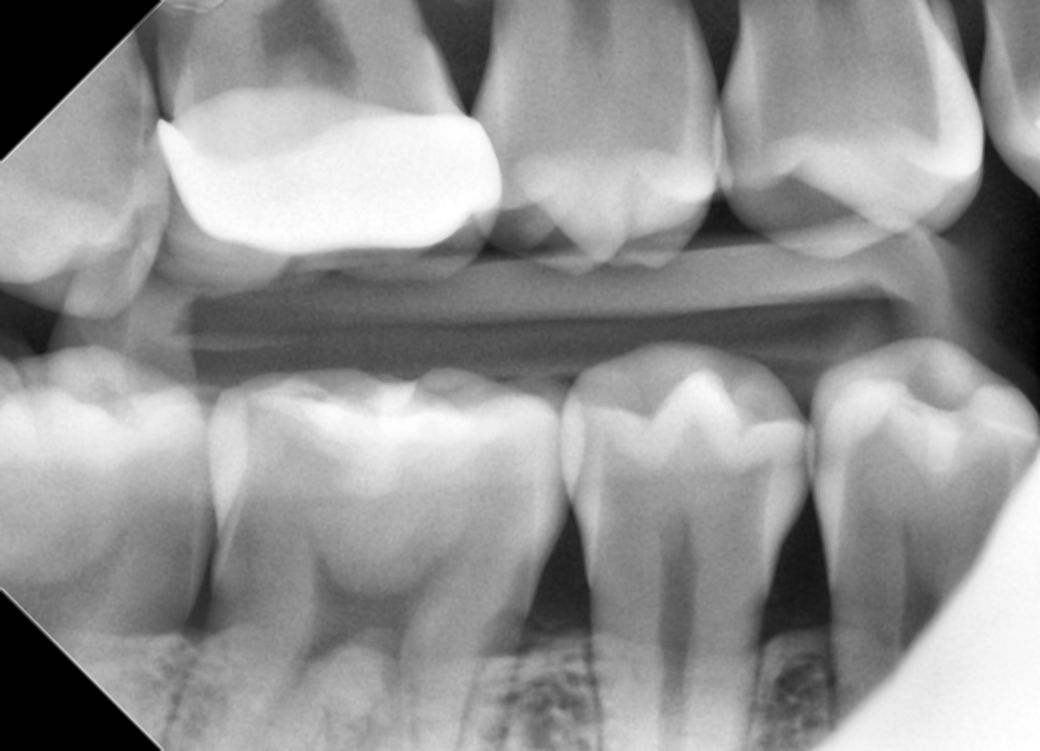

이거 인접면 충치인가요? 여러군데 갔는데 헷갈려요

오른쪽 상악 어금니인데 총 3군데 치과를 갔습니다 원래 1면전부터 이부분에 깨진면이 있었습니다 이 부분을 첫번째 치과에서 바이트윙 찍고 인접면 충치가 있어서 신경치료 가능성까지 언급하시더라고요 그래서 두번째 치과를 갔는데 육안이랑 파노라마까지만 보시고 없다고 깨진부분만 레진으로 떼워주셨어요 그래도 미심쩍어서 세번째 치과갔는데 여기는 이 파노라마랑 육안에 넣고보는 카메라로 보셨는데 여기도 없다고 하시더라고요 첫번째 같이 심한데 두곳이 모른걸까요 아니면 별로 없는것 같나여 보기에는 둘다 맞아보여서 질문합니다

• 2번 째 사진

1. 충치가 있는것은 맞습니다. 원래 인접면 우식의 경우 교합면보다 신경과 거리가 짧기 때문에 신경치료 가능성은 루틴하게 언급됩니다.

3. 해당 부위 충치가 생긴 건 아무래도 그 앞 크라운의 마진이 아주 핏하게 맞지 않기 때문입니다. 그 사이로 계속 침과 음식물이 끼어 들어가니 충치가 생길 수 밖에 없죠. 평소에도 본인이 해당 부위 음식물이 잘 낀다고 느꼈다면 크라운 재제작을 하여 문제를 적극적으로 해결하거나 아니면 적어도 해당 부위 치실이나 치간칫솔로 아주 꼼꼼하게 관리해주셔야 합니다.

일단 바이트 윙 사진에서는 인접면 충치가 없어 보입니다 두번째 치과에서 파노라마 찍고 레진 치료 하신 거 같고 세번째 치과에서 눈으로 보시니 인접면 충치가 없고 레진 치료까지 했으니 정상이라고 한거 같습니다 아무튼 현재 상태는 이제 정상 소견 같아 보이니 너무 걱정 않으셨으면 합니다